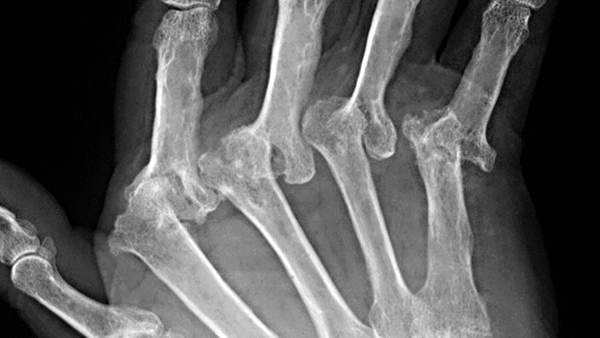

Rheumatoid arthritis (RA) refers to a painful auto-immune degenerative arthritic medical condition that is a chronic inflammatory disease. It affects approximately 1% of the United States population.

RA often results in pain and inflammation in joints on both sides of the body, and can render patients with disability due to its effect on the immune system and to the joints and body parts.

RA is classified as an autoimmune disease—a condition where the patient's own body’s immune system attacks its own tissues. Although the exact cause of RA is not known, multiple theories have been proposed to identify who is most likely to develop it.